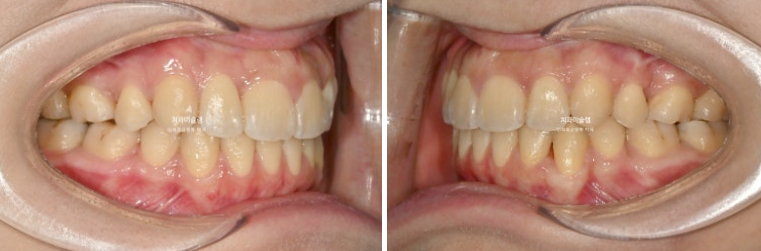

26.01

중심선은 일치하고

어금니 교합은 물샐틈 없는 1급 교합관계를 보이며 쫀쫀하죠 (?)

이제 전후 비교 보여드릴게요

재제작은 총 2회를 진행했고

총 치료기간은 2년 3개월 입니다.

23.10~26.01

개방교합이 해소되어 잘 물립니다

중심선 불일치는 해결이 되었습니다.

교합이 좋습니다.